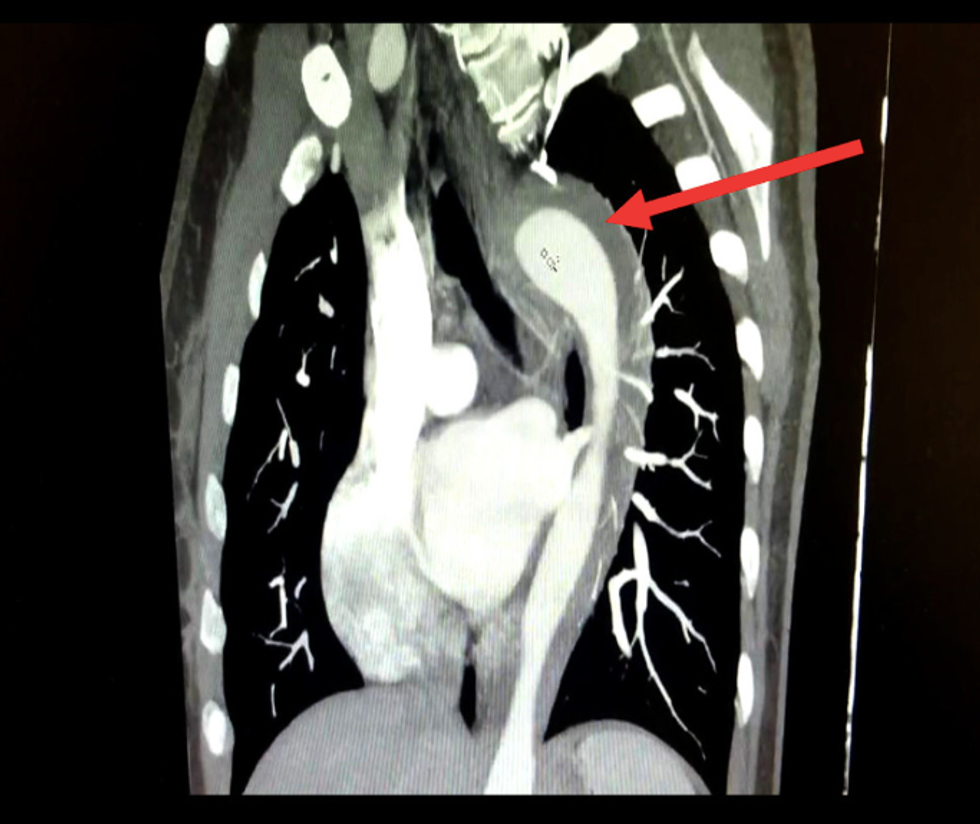

Medics gave the woman morphine and fentanyl to reduce the pain before confirming she had a leak in her aorta, the largest artery in the body which transports blood.

Medically known as an acute aortic syndrome or AAS, the disease can be severely life-threatening, reports the study. Men have a higher chance of developing AAS, and the peak age of diagnosis is later adulthood, around the age of 65.

If left untreated, an aortic rip can lead to death and has instantly killed 40% of sufferers, says the case.